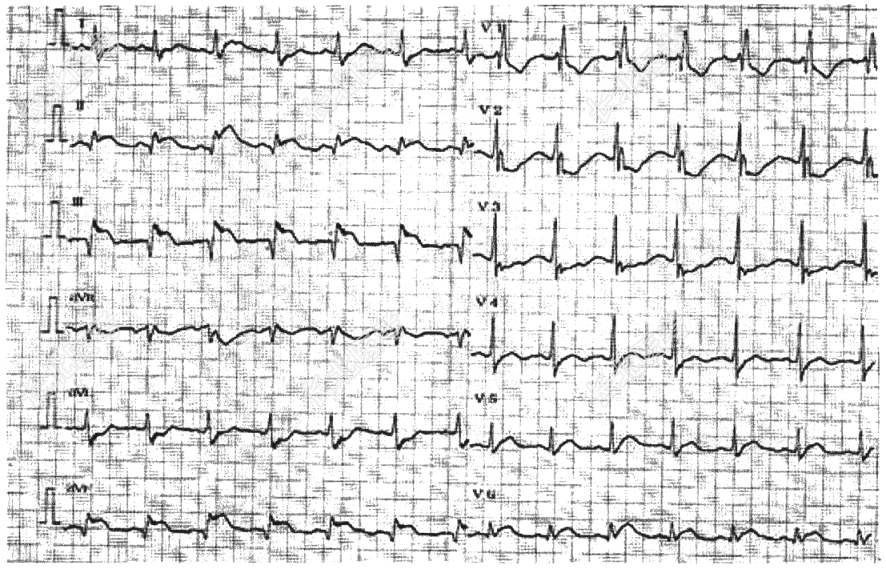

- [材料题] 患者女性,54岁,既往冠心病病史,突发胸痛伴心悸、大汗4小时来诊。查心电图如下,

- 简答题1、诊断为什么疾病?

- 简答题2、心电图上哪些导联的变化有助于诊断急性下壁心肌梗死?